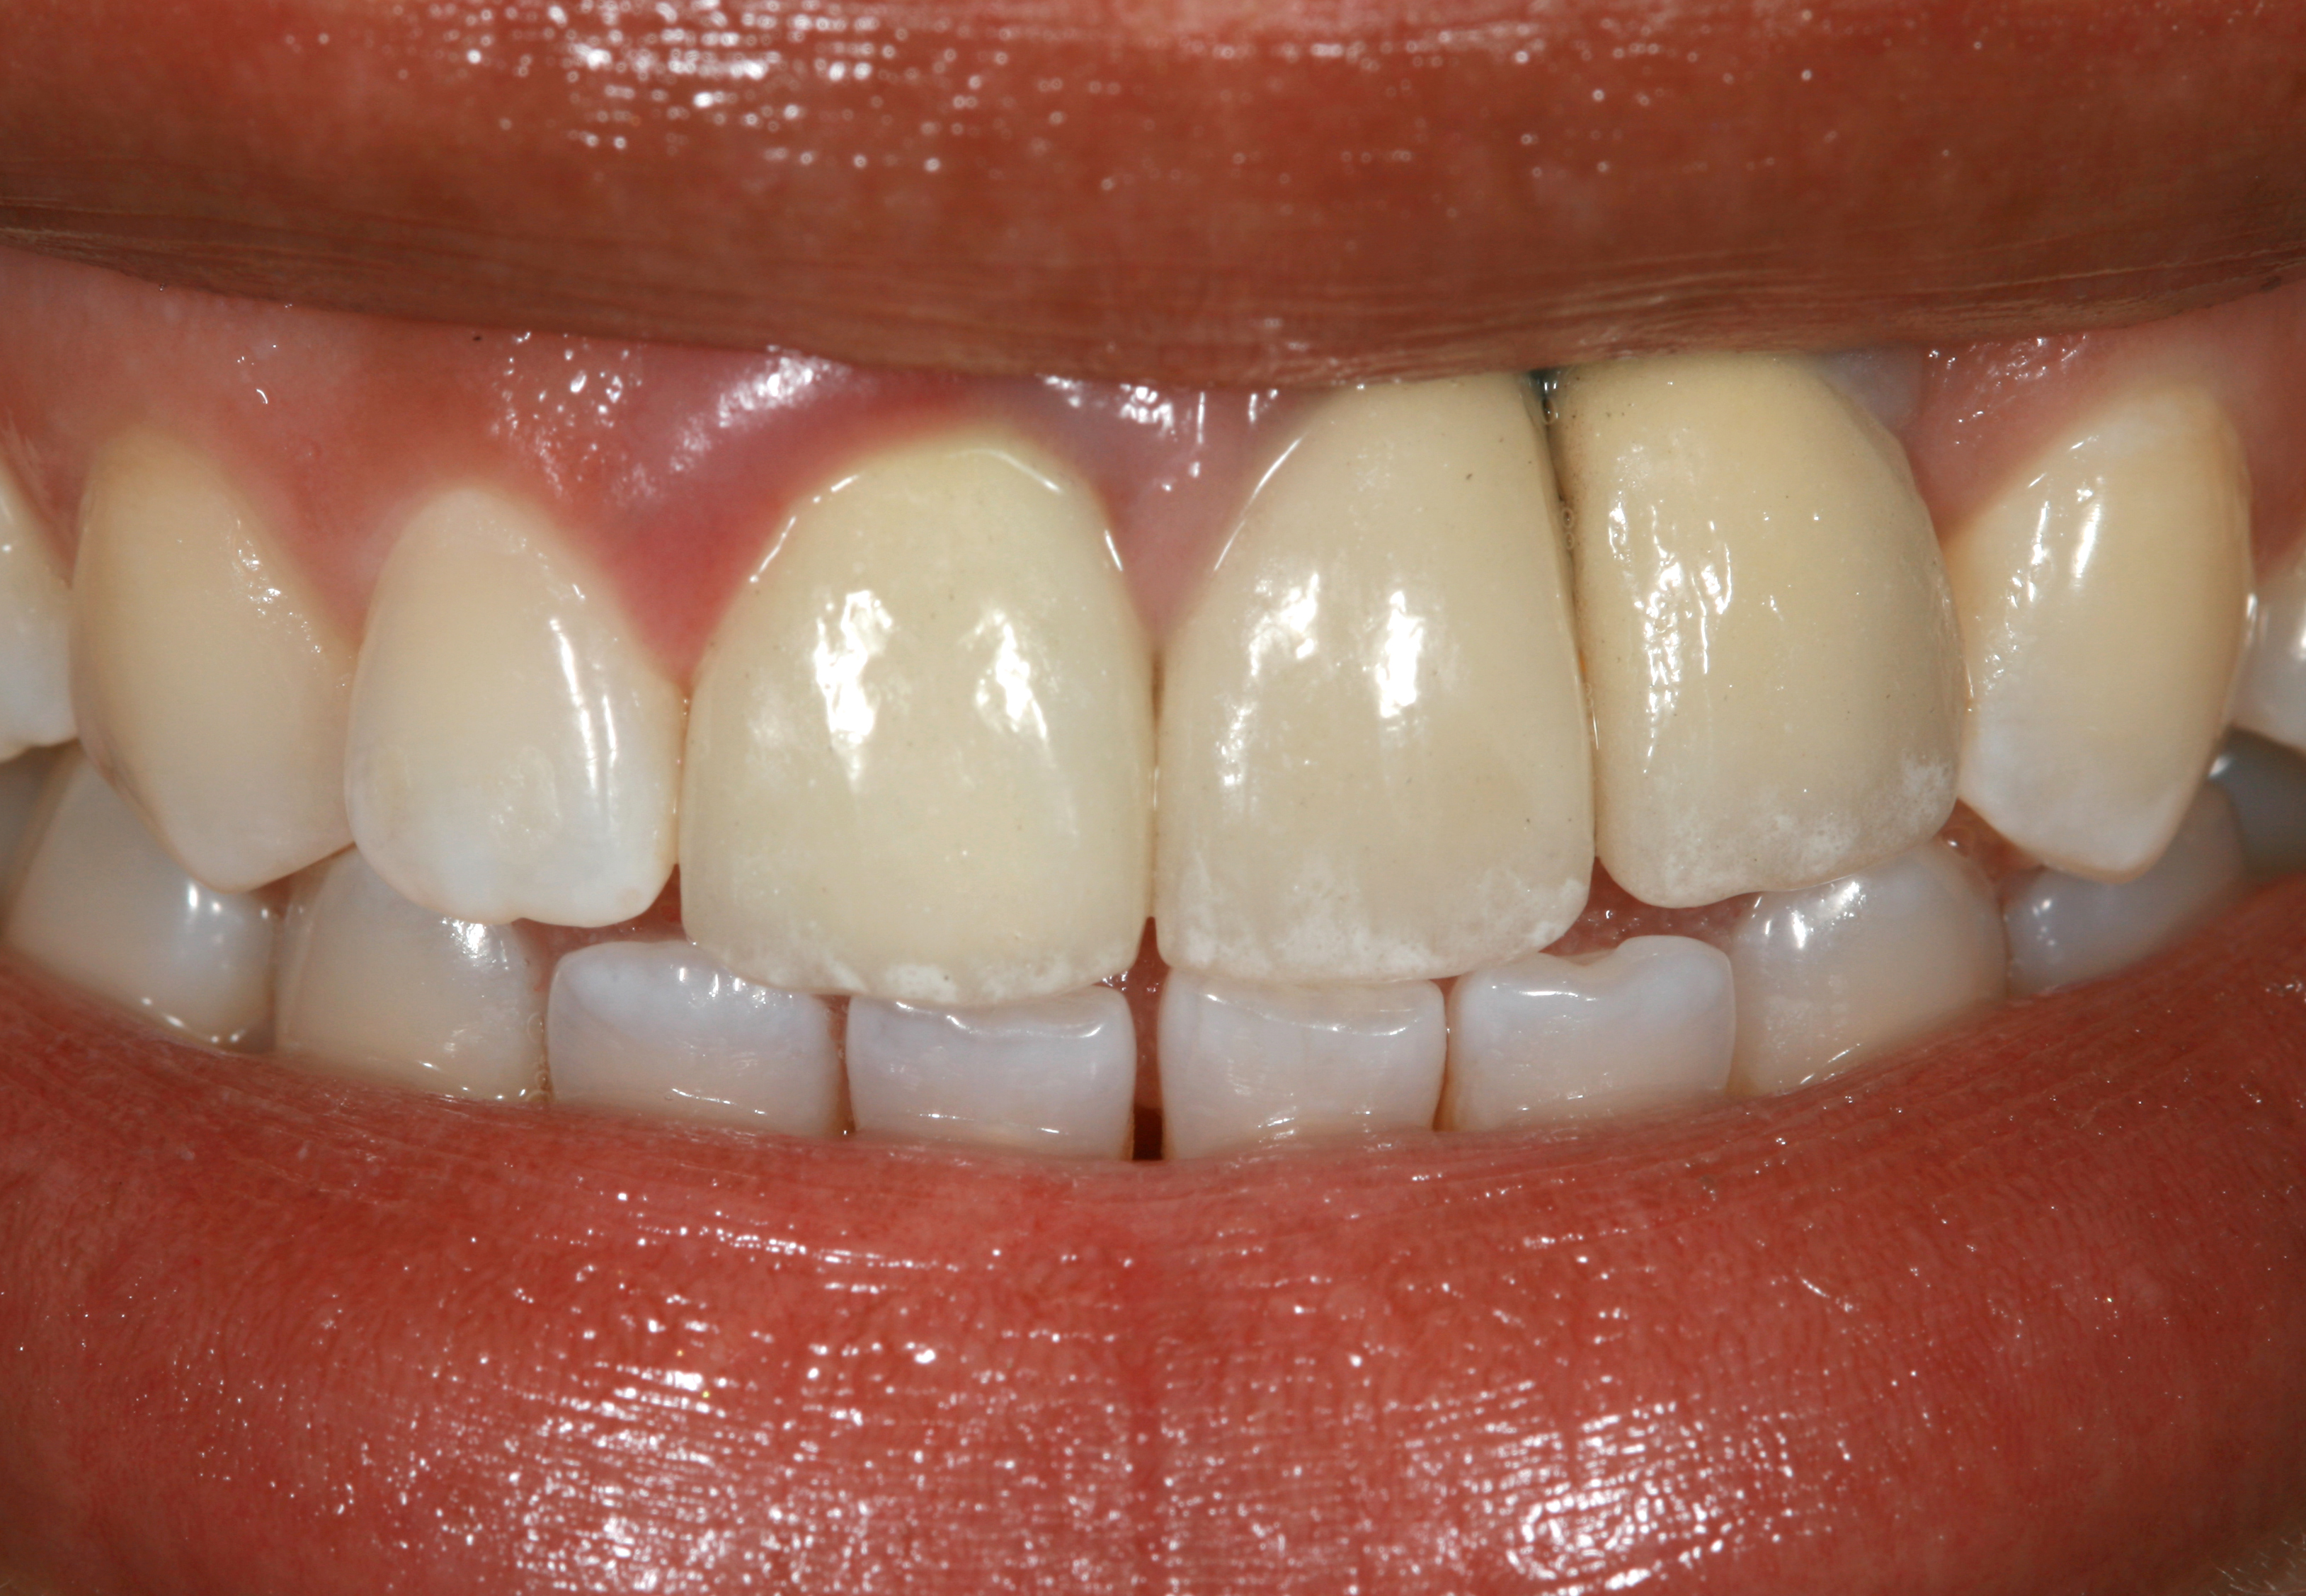

Fig 3. A patient presented with a high smile line and midfacial recession of the maxillary right lateral incisor as evidenced by the increased tooth length compared with the contralateral lateral incisor.

Figure 3

Fig 4. Intraoral view of tooth No. 7 with the gingival zenith more apical than the adjacent central incisor and canine tooth.

Figure 4